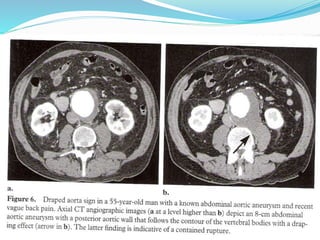

 Imaging findings of A. aneurysm rupture vary from impending

rupture to contained rupture from small aortic leaks with subtle

infiltration of retroperitoneal fat to frank retroperitoneal or intra

peritoneal extra vasation

 CECT

 Active extravasation of contrast noted

 Draped aorta sign

 post wall of aorta is not identifiable or it closely follows the

contour of adjacent vertebral bodies, a consequence of a deficient

aortic wall